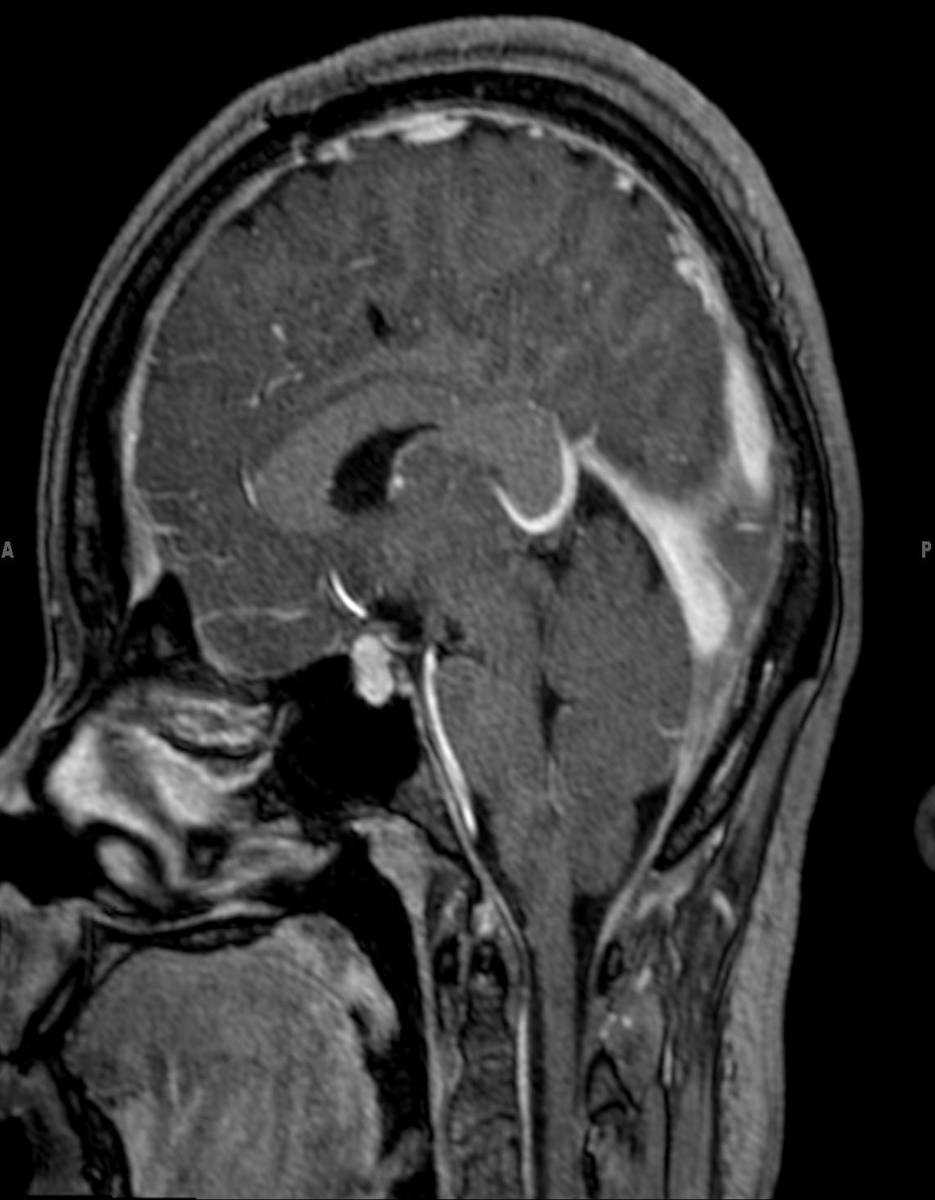

This is a case of Langerhans Cell Histiocytosis, or LCH, of the pituitary gland and infundibulum in a 6-year-old male. The first image is sagittal T1-weighted with some motion degradation. There is thickening of the infundibulum and pituitary gland itself, with classic loss of the typically hyerintense posterior pituitary. The second image is a noncontrast coronal T1 correlate redemonstrating infundibular thickening as well as enlargement of the pituitary gland itself. The third image is with T2 weighting in the coronal plane redemonstrating thickening of the pituitary stalk. The fourth through sixth images are multi planar postcontrast T1-weighted sequences demonstrating avid post contrast enhancement of the markedly enlarged infundibulum and pituitary gland itself. LCH is a reactive clonal disease of the monocyte-macrophage system, and may affect almost any organ system. LCH CNS involvement may fall into one of several forms such as: osseous lesions with or without soft tissue components, intra-cranial extra-axial lesions, such as in the hypothalamic-pituitary region, meninges, or circumventricular organs, intracranial intra-axial lesions and cerebral atrophy. Langerhans cell histiocytosis is the most common cause of infundibular thickening in childhood. Diabetes insipidus is the typical clinical presentation of hypothalamic-pituitary involvement.